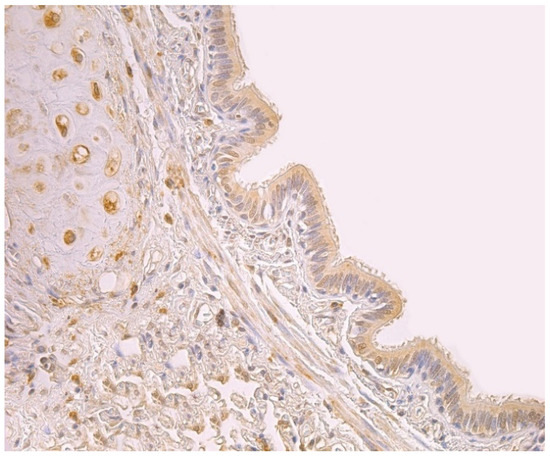

3.2. Immunohistochemical (IMH) Data